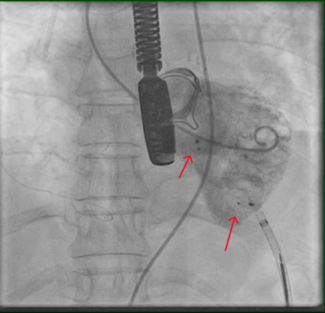

A 0.014” BMW guidewire (Abbott Vascular) was then used to cross into the LCX to perform PCI to the OM immediately distal to a posterolateral branch. While trying to cross with a stent (2.5 mm x 15 mm Promus platinum-chromium DES [Boston Scientific]) through the LMCA into the LCX, the stent was detached from the delivery balloon, subsequently jamming the ostial LAD stent (Figure 1C). This precluded the possibility to further advance the stent to the distal segment of the OM and prevented deployment at the actual detached position due to the compromise of the LMCA, LAD ostial stent, and LCX, which were not the intended segments to treat. Fortunately we were able to maintain wire position across the non-expanded stent. A new 1.5 mm x 12 mm Sprinter coronary balloon (Medtronic) was positioned distal to the detached stent (Figure 2A), and applying low atmospheres for its inflation, we pulled the system (balloon-stent-guidewire-guiding catheter) back into the distal radial artery and removed it, including the glide sheath, without damaging the radial artery.

A 0.014” BMW guidewire (Abbott Vascular) was then used to cross into the LCX to perform PCI to the OM immediately distal to a posterolateral branch. While trying to cross with a stent (2.5 mm x 15 mm Promus platinum-chromium DES [Boston Scientific]) through the LMCA into the LCX, the stent was detached from the delivery balloon, subsequently jamming the ostial LAD stent (Figure 1C). This precluded the possibility to further advance the stent to the distal segment of the OM and prevented deployment at the actual detached position due to the compromise of the LMCA, LAD ostial stent, and LCX, which were not the intended segments to treat. Fortunately we were able to maintain wire position across the non-expanded stent. A new 1.5 mm x 12 mm Sprinter coronary balloon (Medtronic) was positioned distal to the detached stent (Figure 2A), and applying low atmospheres for its inflation, we pulled the system (balloon-stent-guidewire-guiding catheter) back into the distal radial artery and removed it, including the glide sheath, without damaging the radial artery.

We decided to gain right femoral artery access in order to use a 7 Fr system to improve guiding catheter support, alignment, and to protect the LAD during performance of a certainly difficult procedure. The first angiogram showed the presence of a longitudinal compression of the ostial LAD stent (Figure 2B) probably due to the previous forceful withdrawal of the detached and jammed stent with secondary and involuntary deep guiding catheter intubation. We decided to wire the LCX and the LAD with BMW guidewires and, taking advantage of the longitudinal compression of the LAD stent, we were able to easily advance balloons and stents into the distal segments of the OM (Figure 3A). Then 2 non-overlapped Endeavor Resolute DES (2.5 mm x 18 mm an 2.75 mm x 24 mm) were delivered to the LCX without difficulties, resulting in a good final angiographic result with no further compromise of the ostial LAD stent.